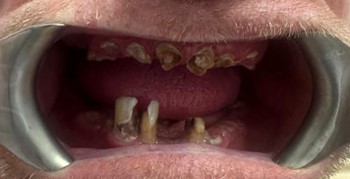

Full Arch All-On-X Dental Implants - Before

BEFORE

This patient presented with significant dental concerns affecting both oral function and smile appearance. Everyday activities such as eating, speaking, and smiling comfortably had become increasingly difficult.

Like many people exploring full mouth dental implants, the patient was seeking a fixed and reliable solution that could restore both confidence and quality of life.

The patient visited Sayers Dental feeling frustrated with his remaining broken teeth and was ready for a fresh start. He wanted to eat comfortably, improve his appearance, and regain the confidence to smile again.